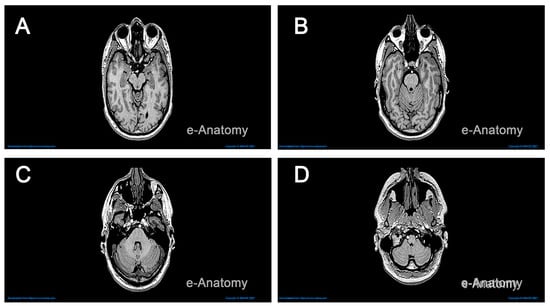

2.1. Data Collection

2.2. Computer-Aided Modeling